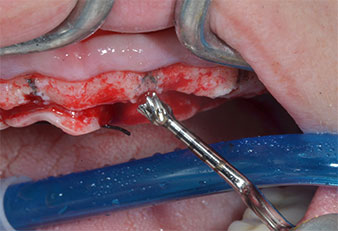

Para marcar las posiciones del implante y realizar la preparación piloto, se utilizó un inserto piezoeléctrico (Piezomed I1) con revestimiento de diamante y forma de llama (figura 3). Se tomaron precauciones para realizar movimientos hacia arriba y hacia abajo, con una potencia reducida, una irrigación completa y una baja presión (por debajo de 300 g). A continuación, se aplicó un inserto piloto (Piezomed I2A/I2P) para aumentar el diámetro inicial de 2 mm de los sitios de implante (figura 4), seguido de un inserto de 3 mm (Fig. 5).